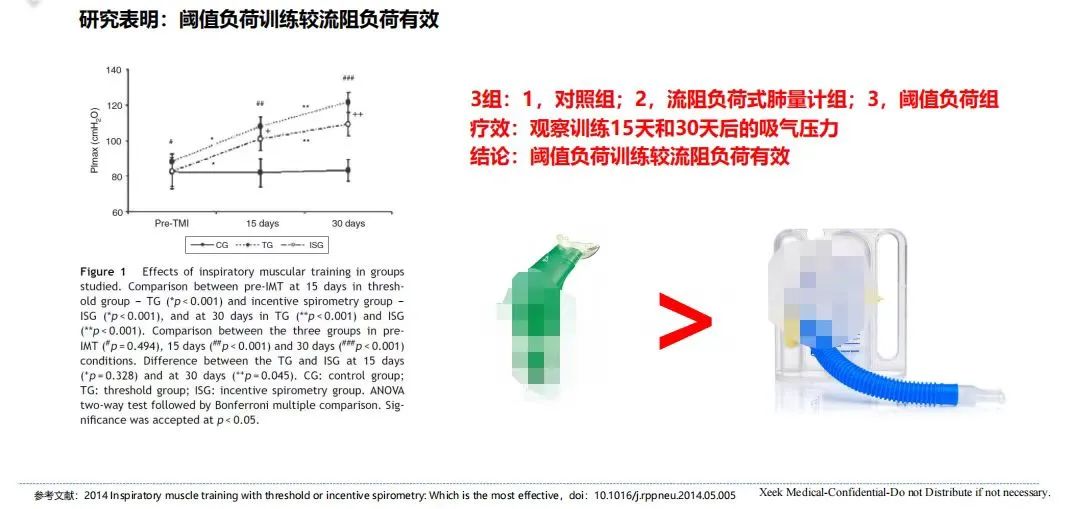

渐减式流(liú)阻呼吸训练(liàn)器开阀门的(de)数值是起始数值,这个值是(shì)固定值,因此刚(gāng)开始训练(liàn)时需要(yào)产生一定的压力克服阈值(zhí)负荷从而打(dǎ)开阀门,也就训练初要尽可能快速、用力吸气/呼气;当阀门(mén)打开(kāi)后(hòu),阻抗就变(biàn)为动(dòng)态(tài)的,并随(suí)着(zhe)吸(xī)气/呼气(qì)压力(lì)的(de)逐渐(jiàn)降低而渐减。渐减式流(liú)阻负(fù)荷的训练方式适应了呼吸系统的压力(lì)-容量(liàng)关系,在相同阻力(lì)下,使用渐减式流阻负荷(hé)训(xùn)练,可以使吸气容量更高,且阻(zǔ)抗伴随整(zhěng)口气,这样不仅(jǐn)大大减(jiǎn)少呼吸肌损伤,也达到训练的最佳效果。目前市(shì)面上的渐减(jiǎn)式流阻(zǔ)负荷呼吸训练器大多(duō)可(kě)搭配App/PC软件使(shǐ)用,不(bú)少研究表明渐(jiàn)减式流(liú)阻负荷训练较目标流阻负荷训练、阈(yù)值负荷(hé)训练效果更佳。

3 种呼吸训练(liàn)器(qì)的研究对比